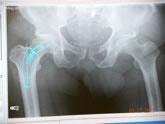

| Pre-op templating |

His own templating process |

Determining neck resection |

Photos from His First Case

JISRF is pleased that Dr. Mackel has agreed to help define the indications and contraindications on Neck Stabilized Stems for THA and as part of that process, what are the learning curves to preoperative planning (templating). Lateral templating appears to be key in determining stem size and A/P helps to determine level of neck resection (leg length) and femoral offset. |